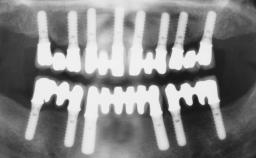

Immediate Loading of Six Implants in the Maxilla and Final Restoration with a Full-Arch CAD/CAM Zirconia FDP

A 63-year-old male patient was referred for a consultation and treatment of partial edentulism in the maxilla. The patient presented with residual anterior teeth and declined a partial removable prosthesis. He reported that the maxillary posterior teeth had been extracted due to mobility and periodontal disease two months before the consultation. The patient’s chief complaint was that his residual maxillary teeth were mobile and that he was unable to chew. The patient’s desire was a stable and comfortable fixed maxillary rehabilitation. The patient was a light smoker (fewer than 10 cigarettes/ day), and his medical history was without significant findings. He was not on any regular medication at the time of consultation. The extraoral examination revealed a normal physiognomy with a correct distribution of the facial thirds. The patient presented a low lip line, and the transition line between teeth and soft tissues was not exposed during a forced smile.

# of Implants 6

Type of Implants One-Piece

Defining Characteristics Fully edentulous upper jaw to be rehabilitated with four or more implants

Modality 6+ implants with immediate loading

Loading Protocol Immediate

Retention Cemented, with prosthesis margin < 3mm submucosal Cemented, with prosthesis margin < 3mm submucosal